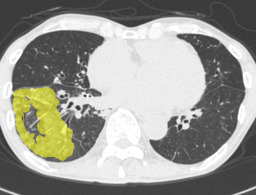

In this paper, we define partial annotation as an annotation format in which only one class is chosen for the annotation and only pixels belonging to the chosen class are annotated per image. For example, in Figure 1(a), although there is ground glass opacity in the image, only consolidation is chosen for annotation and pixels of consolidation are annotated. Partially annotated dataset is less informative for training, however, it is much easier to create compared to fully annotated dataset since annotators only need to focus on one class at a time during the annotation task.

Statistics of our dataset are shown in Table 1 and typical images and their annotations for each DLD pattern are shown in Figure 1. In our partially annotated dataset, all the pixels in a slice were manually classified into two classes: dominating DLD pattern and other tissues. In other words, all the pixels in our dataset were assigned one of the labels from either of the two label sets, Lstrong={lCON,lGGO,lHCM,lEMP,lNOR}subscript𝐿𝑠𝑡𝑟𝑜𝑛𝑔subscript𝑙𝐶𝑂𝑁subscript𝑙𝐺𝐺𝑂subscript𝑙𝐻𝐶𝑀subscript𝑙𝐸𝑀𝑃subscript𝑙𝑁𝑂𝑅L_{strong}=\{l_{CON},l_{GGO},l_{HCM},l_{EMP},l_{NOR}\} or Lweak={lCON¯,lGGO¯,lHCM¯,lEMP¯,lNOR¯}subscript𝐿𝑤𝑒𝑎𝑘subscript𝑙¯𝐶𝑂𝑁subscript𝑙¯𝐺𝐺𝑂subscript𝑙¯𝐻𝐶𝑀subscript𝑙¯𝐸𝑀𝑃subscript𝑙¯𝑁𝑂𝑅L_{weak}=\{l_{\overline{CON}},l_{\overline{GGO}},l_{\overline{HCM}},l_{\overline{EMP}},l_{\overline{NOR}}\}. For example, in Figure 1(a), colored pixels were labeled as lCONsubscript𝑙𝐶𝑂𝑁l_{CON} and all the other pixels were labeled as lCON¯subscript𝑙¯𝐶𝑂𝑁l_{\overline{CON}}. In this paper, we call pixels of label lLweak𝑙subscript𝐿𝑤𝑒𝑎𝑘l\in L_{weak} and lLstrong𝑙subscript𝐿𝑠𝑡𝑟𝑜𝑛𝑔l\in L_{strong} as weakly annotated pixels and strongly annotated pixels respectively. Our pixel-wise annotations were created in the following steps. First, up to 3 slices were chosen for the annotation for each HRCT scan and for each slice, one representing DLD pattern was chosen by a radiologist. Second, three radiologists performed pixel-wise binary annotation (e.g. binary annotation between lCONsubscript𝑙𝐶𝑂𝑁l_{CON} or lCON¯subscript𝑙¯𝐶𝑂𝑁l_{\overline{CON}}) for each slice. Finally, the radiologists’ annotations were merged by taking majority classes for each pixel (i.e. pixels labeled as a DLD pattern by more than 2 radiologists became the corresponding DLD pixel). In addition to the DLDs annotation, lung fields were manually segmented under the supervision of radiologists and training and testing were conducted only within the lung fields.

Figure 1: Typical slices for each DLD classes. Slices of HRCT are shown in lung window setting (window-center=-600, window-width=1500) with annotated labels superimposed in transparent colors. Note that even if more than one DLD patterns existed, only one DLD pattern was chosen and annotated for a slice to facilitate the annotation process.